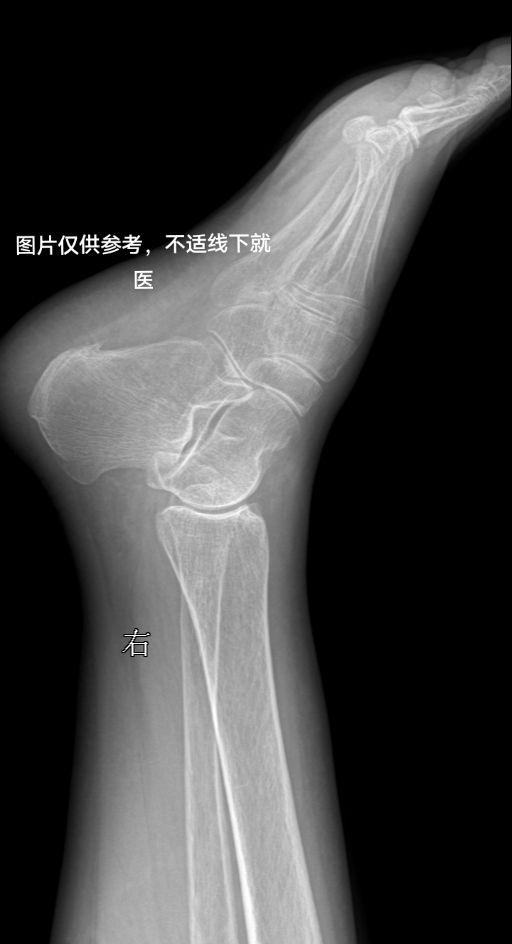

右足底疼痛

2024-07-30 16:36